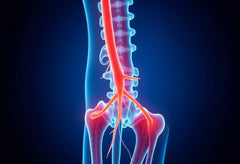

Ein Bandscheibenvorfall in der Brustwirbelsäule, insbesondere an den Wirbeln BWS 11/12, ist ein seltenes, aber potenziell schmerzhaftes Gesundheitsproblem. Die Brustwirbelsäule, die sich zwischen Hals- und Lendenwirbelsäule befindet, ist weniger beweglich als andere Teile der Wirbelsäule, was sie zu einem eher ungewöhnlichen Ort für Bandscheibenvorfälle macht. Dennoch können Vorfälle in diesem Bereich erhebliche Beschwerden verursachen und die Lebensqualität der Betroffenen stark beeinträchtigen.

Ein Bandscheibenvorfall in der Brustwirbelsäule, insbesondere an den Wirbeln BWS 11/12, ist ein seltenes, aber potenziell schmerzhaftes Gesundheitsproblem. Die Brustwirbelsäule, die sich zwischen Hals- und Lendenwirbelsäule befindet, ist weniger beweglich als andere Teile der Wirbelsäule, was sie zu einem eher ungewöhnlichen Ort für Bandscheibenvorfälle macht. Dennoch können Vorfälle in diesem Bereich erhebliche Beschwerden verursachen und die Lebensqualität der Betroffenen stark beeinträchtigen.

Die Wirbel BWS 11/12 befinden sich im unteren Teil der Brustwirbelsäule und spielen eine entscheidende Rolle bei der Stabilisierung des Oberkörpers und der Unterstützung der Rippen. Diese Wirbel sind wichtig für die Beweglichkeit und Flexibilität des Rumpfes, insbesondere bei Dreh- und Beugebewegungen. Ein Bandscheibenvorfall in diesem Bereich kann daher nicht nur lokale Schmerzen verursachen, sondern auch weitreichende Auswirkungen auf die gesamte Körperhaltung und Beweglichkeit haben.

Ein Bandscheibenvorfall im Bereich der Brustwirbelsäule, insbesondere an den Wirbeln BWS 11/12, kann eine Vielzahl von Symptomen hervorrufen, die oft schwer zuzuordnen sind. Eines der häufigsten Anzeichen sind Rückenschmerzen, die typischerweise als dumpf und druckempfindlich beschrieben werden. Diese Schmerzen sind meist zwischen den Schulterblättern lokalisiert und können entlang der Brustwirbelsäule auftreten, was die Beweglichkeit stark beeinträchtigen kann.

Zusätzlich zu den lokalen Schmerzen können ausstrahlende Schmerzen auftreten. Diese Schmerzen breiten sich oft in den Brustkorb, die Rippen oder sogar in den Bauchraum aus. In einigen Fällen können sie auch in die Extremitäten, wie Arme und Beine, ausstrahlen. Diese Art von Schmerz kann zu erheblichen Einschränkungen im Alltag führen, da sie häufig bei Bewegungen oder tiefem Einatmen verstärkt werden.